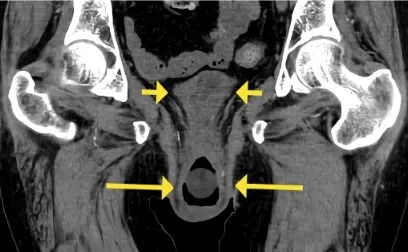

Se realizó una tomografía computarizada abdominal en el tercer día de hospitalización, que mostró hidronefrosis bilateral y prolapso uterino y vesical (figura 1). El catéter vesical se encontraba dentro del prolapso de la vejiga.

Dada la IRA de causa postrenal, se solicitó una evaluación del equipo de ginecología, que recomendó la colocación de un pesario vaginal. Después del procedimiento y 14 días de tratamiento con antibióticos, la función renal regresó a su estado basal.

El prolapso uterino es una condición frecuente, pero la evolución hacia una IRA postrenal ocurre en menos del 5% de los casos. Después de la corrección quirúrgica, generalmente se resuelve la hidronefrosis.

La justificación es que el prolapso uterino causa una torsión de la uretra y retención urinaria. Sin embargo, también puede ocurrir un desplazamiento y torsión de los uréteres, lo que justifica la falta de resolución de la IRA después de la colocación del catéter vesical en el caso clínico.